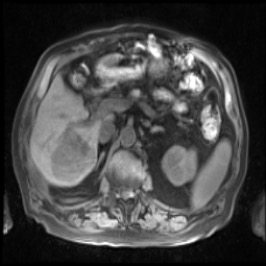

Integrating high-level semantically correlated contents and low-level anatomical features is of central importance in medical image segmentation. Towards this end, recent deep learning-based medical segmentation methods have shown great promise in better modeling such information. However, convolution operators for medical segmentation typically operate on regular grids, which inherently blur the high-frequency regions, i.e., boundary regions. In this work, we propose MORSE, a generic implicit neural rendering framework designed at an anatomical level to assist learning in medical image segmentation. Our method is motivated by the fact that implicit neural representation has been shown to be more effective in fitting complex signals and solving computer graphics problems than discrete grid-based representation. The core of our approach is to formulate medical image segmentation as a rendering problem in an end-to-end manner. Specifically, we continuously align the coarse segmentation prediction with the ambiguous coordinate-based point representations and aggregate these features to adaptively refine the boundary region. To parallelly optimize multi-scale pixel-level features, we leverage the idea from Mixture-of-Expert (MoE) to design and train our MORSE with a stochastic gating mechanism. Our experiments demonstrate that MORSE can work well with different medical segmentation backbones, consistently achieving competitive performance improvements in both 2D and 3D supervised medical segmentation methods. We also theoretically analyze the superiority of MORSE.